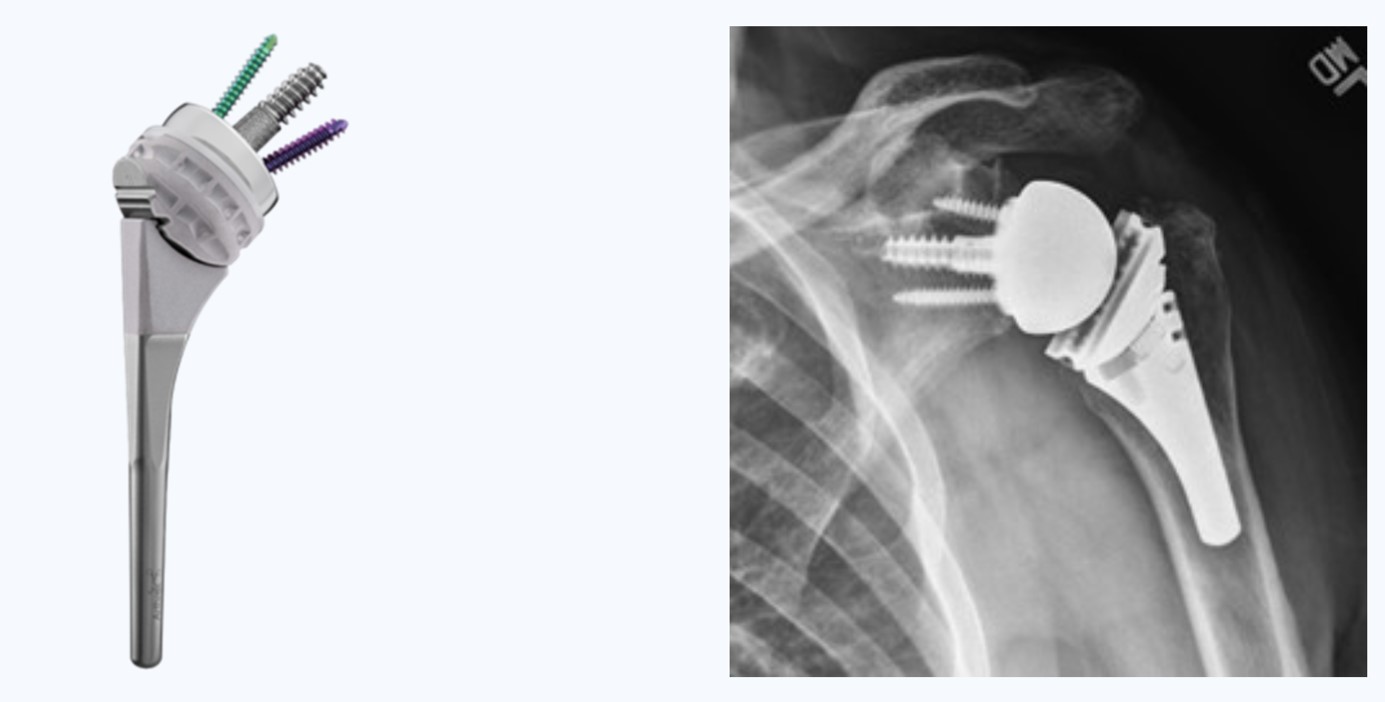

Abban az esetben, ha a tünetek konzervatív kezeléssel nem javulnak, a műtét jelenthet megoldás. A legtöbb esetben a legmegbízhatóbb megoldás az ún. reverz vállprotézis beültetése. Ezt a beavatkozást kombinált (altatás és regionális) érzéstelenítésben végezzük, a váll elülső részén ejtett bemetszéssel és körülbelül 1-1,5 órát vesz igénybe. A vállízületi felszíneket fémből és nagy szilárdságú műanyagból készült protézis komponensekkel cseréljük ki, a fájdalom megszüntetése és a mozgástartomány javítása érdekében. A reverz vállprotézis megakadályozza a felkarcsont elcsúszását a vállcsúcs irányába ezáltal visszaállítja az ízület stabilitását. Ez lehetővé teszi a deltoid izom és a megmaradt vállizmok hatékony működését és a funkció helyreállítását a fájdalomcsillapítás mellett.